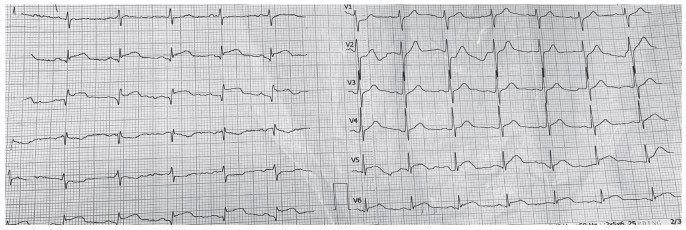

患者于我院急诊完善心电图(2019年5月8日16:33),提示Ⅱ、Ⅲ、aVF、V5-6导联可见ST段抬高0.1~0.2 mV(图 1)。体格检查未见异常阳性体征,体温36.5 ℃,脉率82次/min,呼吸20次/min,血压123/79 mmHg。急诊行冠状动脉造影(2019年5月8日17:15),提示前降支7号段轻度肌桥,余血管未见异常(图 2),急诊行左心室造影,未见异常。

| 图 1 急诊心电图 |